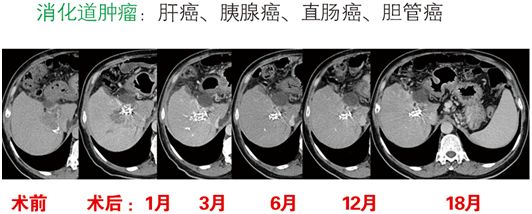

125-碘粒子植入治疗的肿瘤